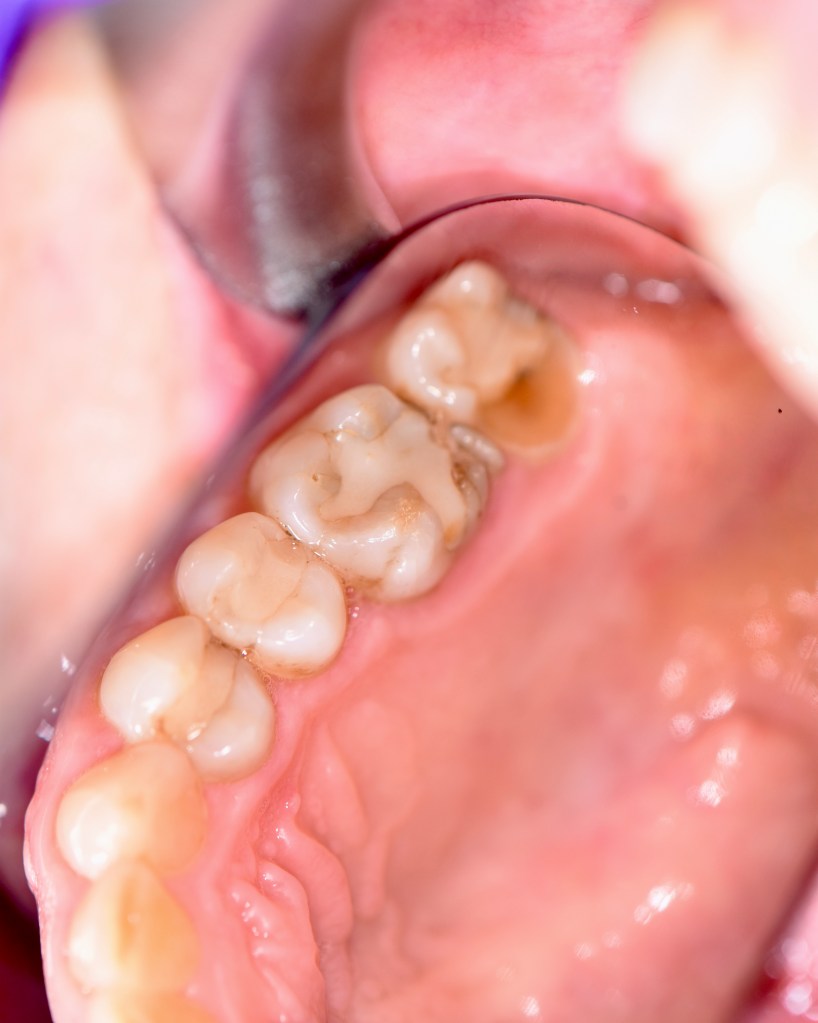

Cavity Broken Metal Filling

Fractured Tooth and Broken Metal Filling